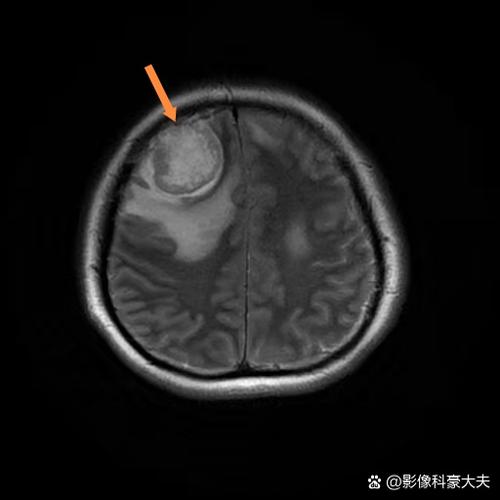

- 脑瘤 (Brain Tumor):是肿瘤性疾病,是脑组织内异常细胞的增生形成的肿块,它通常是一个慢性过程,像“脑内长了个东西”,症状会逐渐加重,但也有部分脑瘤生长迅速。

- 对于脑瘤: 如果出现长期、逐渐加头痛、呕吐、视力问题、癫痫等症状,一定要及时就医,进行头部CT或MRI检查,明确诊断,早发现、早治疗是提高预后的关键。